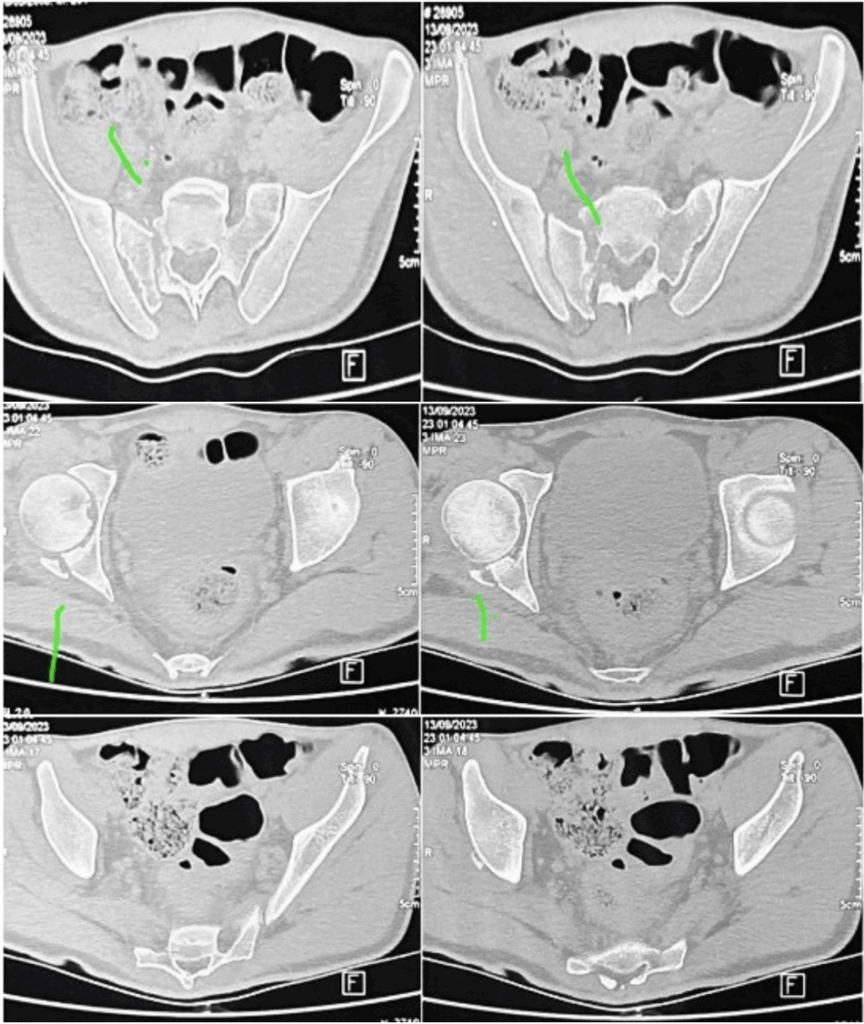

A avaliação detalhada, com exame físico focado em estabilidade articular e integridade neurovascular, aliada a exames de imagem avançados, como tomografia e ressonância magnética, foi fundamental para identificar todas as lesões e planejar o tratamento adequado. Como demonstrado na Figura 4.

Figura 4 – Tomografia Computadorizada de pelve, corte axial após 30 dias de evolução.

Descrição: Observa-se solução de continuidade na região da parede posterior acetabular direita inferior há 50% de acometimento. Solução de continuidade em ramo ísquio púbico esquerdo. Solução de continuidade transforaminal em asa sacral direita.

Fonte: Banco de dados do Hospital de Base Dr. Ary Pinheiro – HBAP.

O manejo inicial seguiu protocolos do ATLS, com redução das luxações, fixação externa e tração, seguido de exames complementares que confirmaram fraturas intrarticulares e lesão ligamentar. A intervenção definitiva incluiu osteossíntese da tíbia (Figura 5), manejo conservador das fraturas pélvicas e acompanhamento ambulatorial com fisioterapia para reabilitação articular e recuperação neurológica parcial.

Figura 5 – Radiografia demonstrando osteossíntese de joelho direito

Descrição: Radiografia AP e perfil realizada pós 180 dias de evolução de osteossíntese com haste centralizada e bem-posicionada. Sinais indiretos de calcificação do complexo ligamentar colateral lateral.